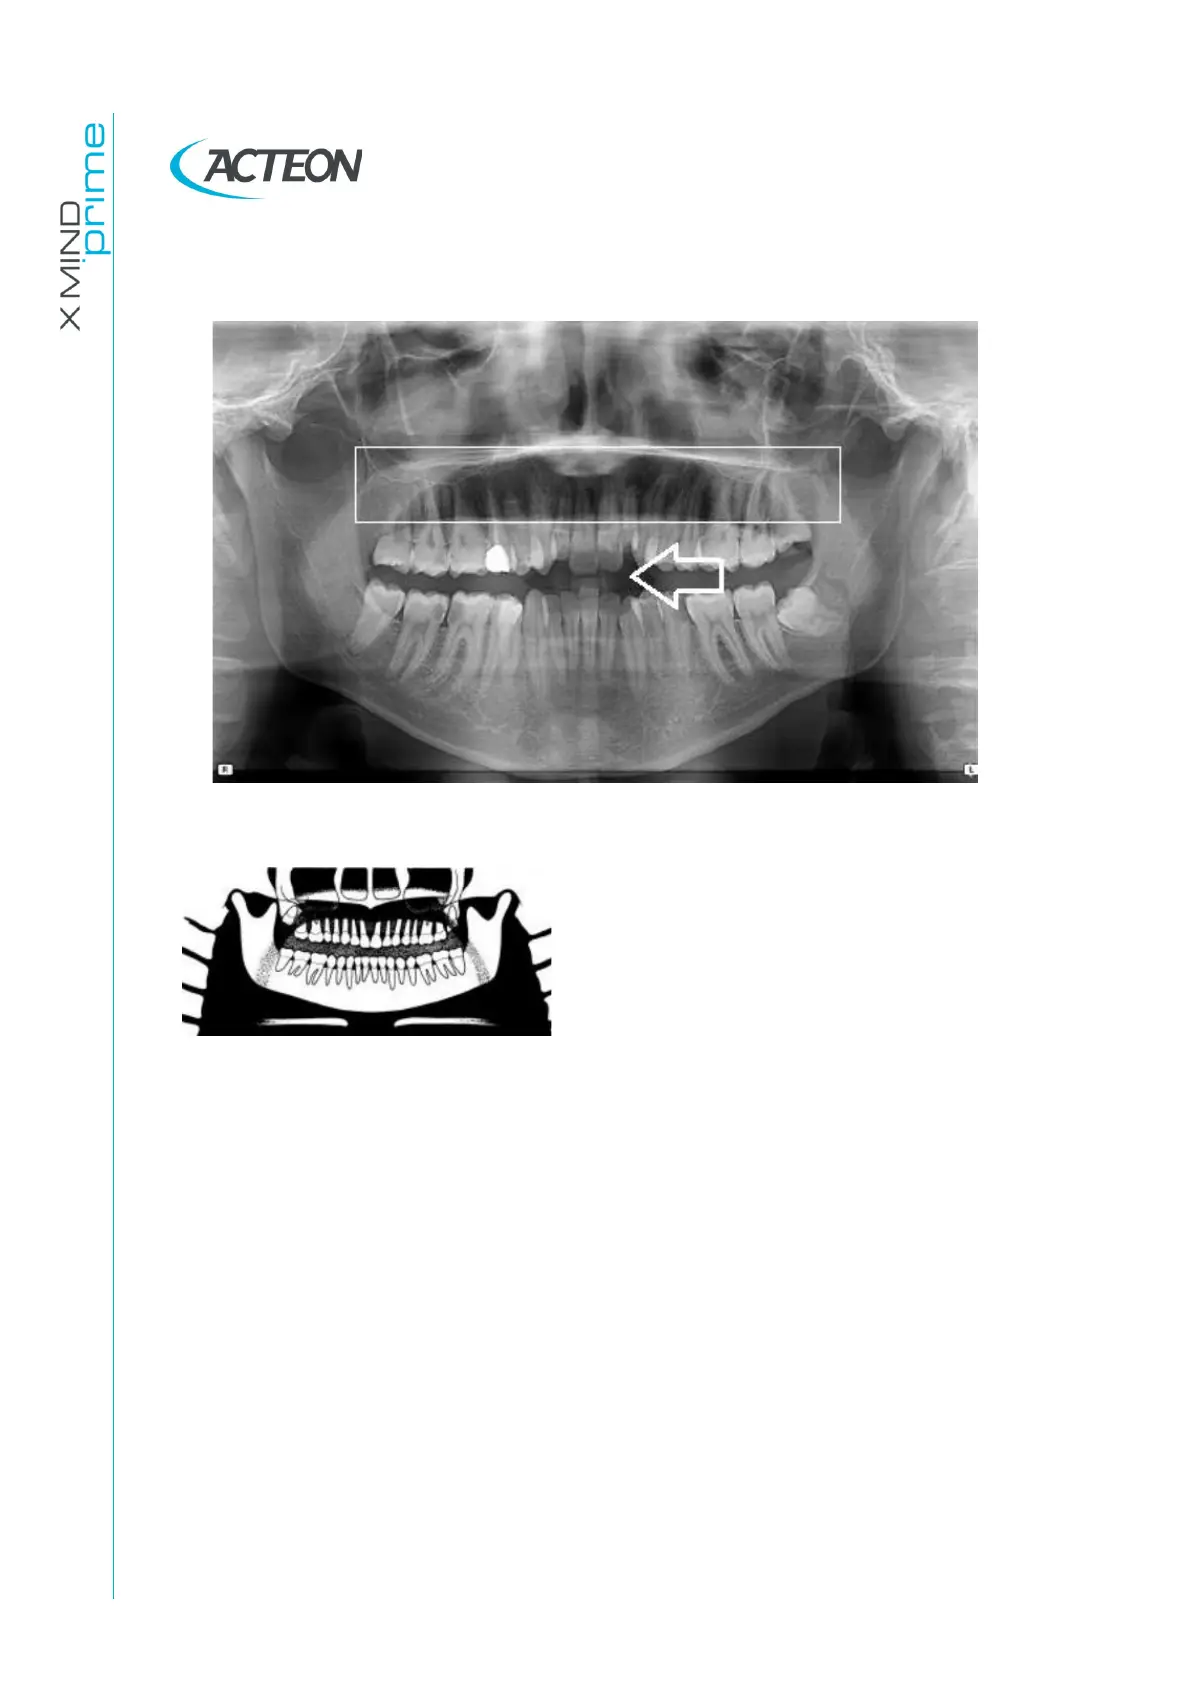

11.2.5 Tongue effect

Figure 38

Problem

The patient’s tongue was not held closely to

the roof of the mouth during the exposure.

Effects

A dark air space between the dorsum of the

tongue and the hard and soft palates

(palatoglossal air spaces) obscures the

apical region of the maxillary teeth.